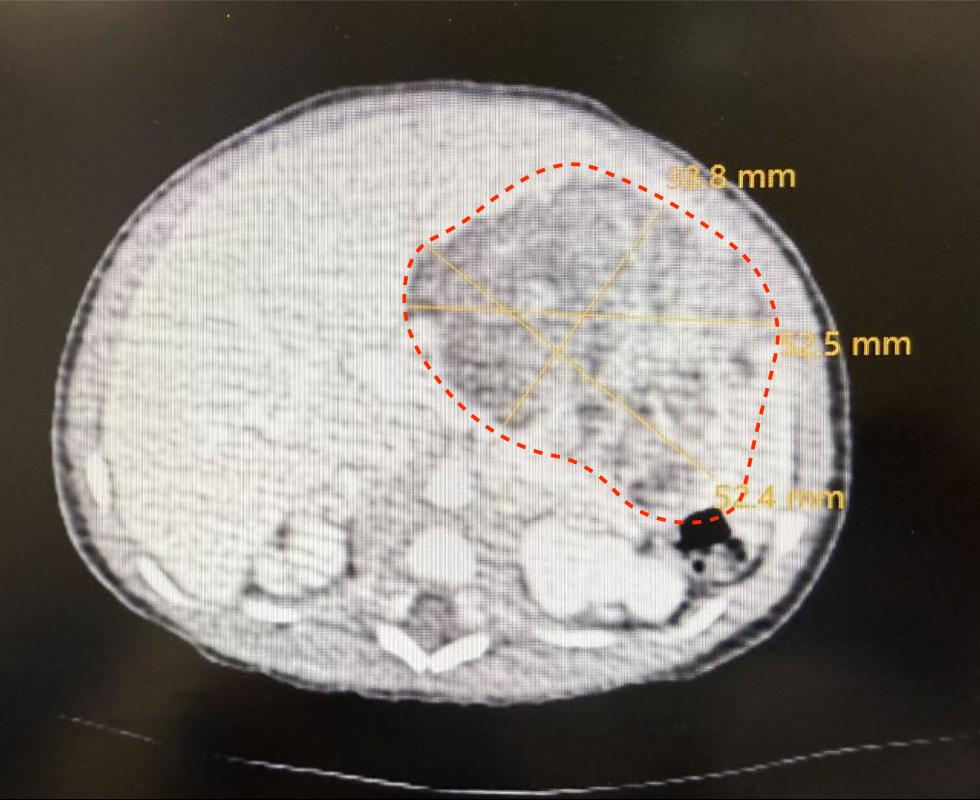

手术的成功,始于术前一次至关重要的“精准侦察”——针对新生儿的多学科协作增强CT检查,这远非一次普通的拍片。“新生儿的增强CT检查,本身就是一次高难度的多学科配合演练。”西安交大一附院医学影像科副主任郭建新介绍。由于患儿肿瘤血供复杂,位置紧邻重要血管与脏器,必须通过静脉注射造影剂进行增强扫描,才能获得清晰的“作战地图”。然而,新生儿血管细如发丝、循环系统脆弱,造影剂的剂量、流速必须极度精确,且检查过程中患儿必须绝对安静,任何移动都会导致图像失效。这就需要一个精密配合的“铁三角”:儿童外科医生提出对影像的具体需求;医学影像科团队量身定制低辐射剂量、快速扫描方案,并精确计算造影剂用量;在麻醉科团队协作下,最终生成了清晰的显示肿瘤与周围组织结构关系的CT图像,为手术精准并完整切除肿瘤病灶提供了可靠依据。

有了影像与麻醉基础,交大一附院陆港院区儿童外科刘仕琪教授团队开始了肿瘤精准切除。凭借术前影像的清晰引导,团队迅速明确肿瘤源于胃壁。在手术团队精确操作下,历时2小时40分钟,肿瘤被完整切除,术中有效保护好相邻重要器官与组织。术后,患儿转入新生儿科监护室,目前已顺利脱离呼吸机,开始经口喂养,即将转入普通病房。